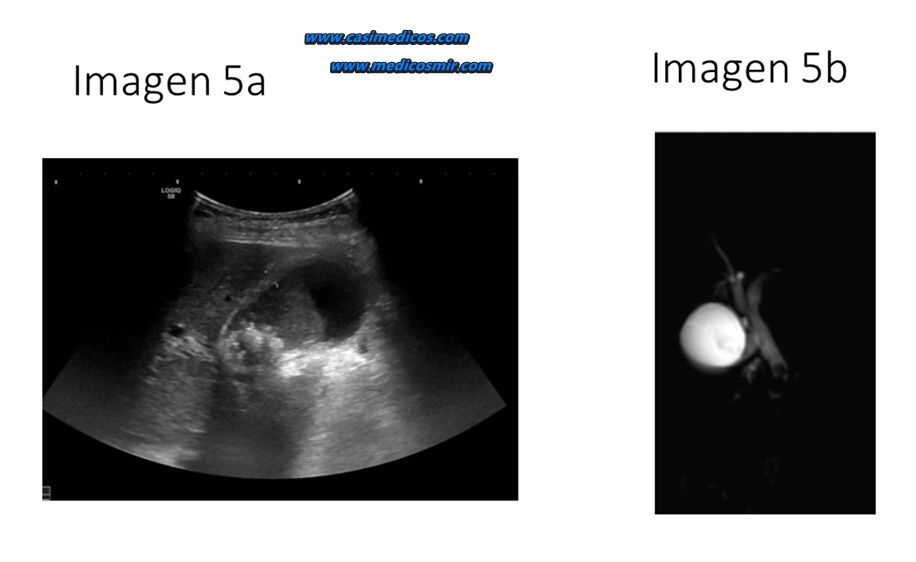

Varón de 58 años con antecedente de colelitiasis en una ecografía abdominal que se hizo por otra causa. Refiere dolor abdominal continuo en epigastrio–hipocondrio derecho que irradia hacia la espalda. El dolor le ha comenzado tras la ingesta y ha cedido parcialmente tras tomar un espasmolítico. Así mismo refiere que se nota un poco amarillo y que la orina es muy oscura. Constantes: Tensión arterial 140/75 mmHg; Frecuencia cardiaca 100 lpm; Temperatura 36,8 °C. A la exploración presenta dolor a la palpación en hipocondrio derecho con signo de Murphy negativo. En la analítica de sangre: Bilirrubina total de 4 mg/dl con bilirrubina directa de 3,5 mg/dl, amilasa y lipasa normal, no tiene leucocitosis. ¿Cuál es la sospecha diagnóstica y tratamiento que aplicarías? Usa las imágenes de ayuda (IMÁGENES 5a y 5b).

Comentario: Ecografía abdominal con colelitiasis y colangio-RM con defecto de repleción en colédoco compatible con coledocolitiasis, en paciente con clínica de obstrucción de vía biliar. El tratamiento de elección es CPRE y posterior colecistectomía.